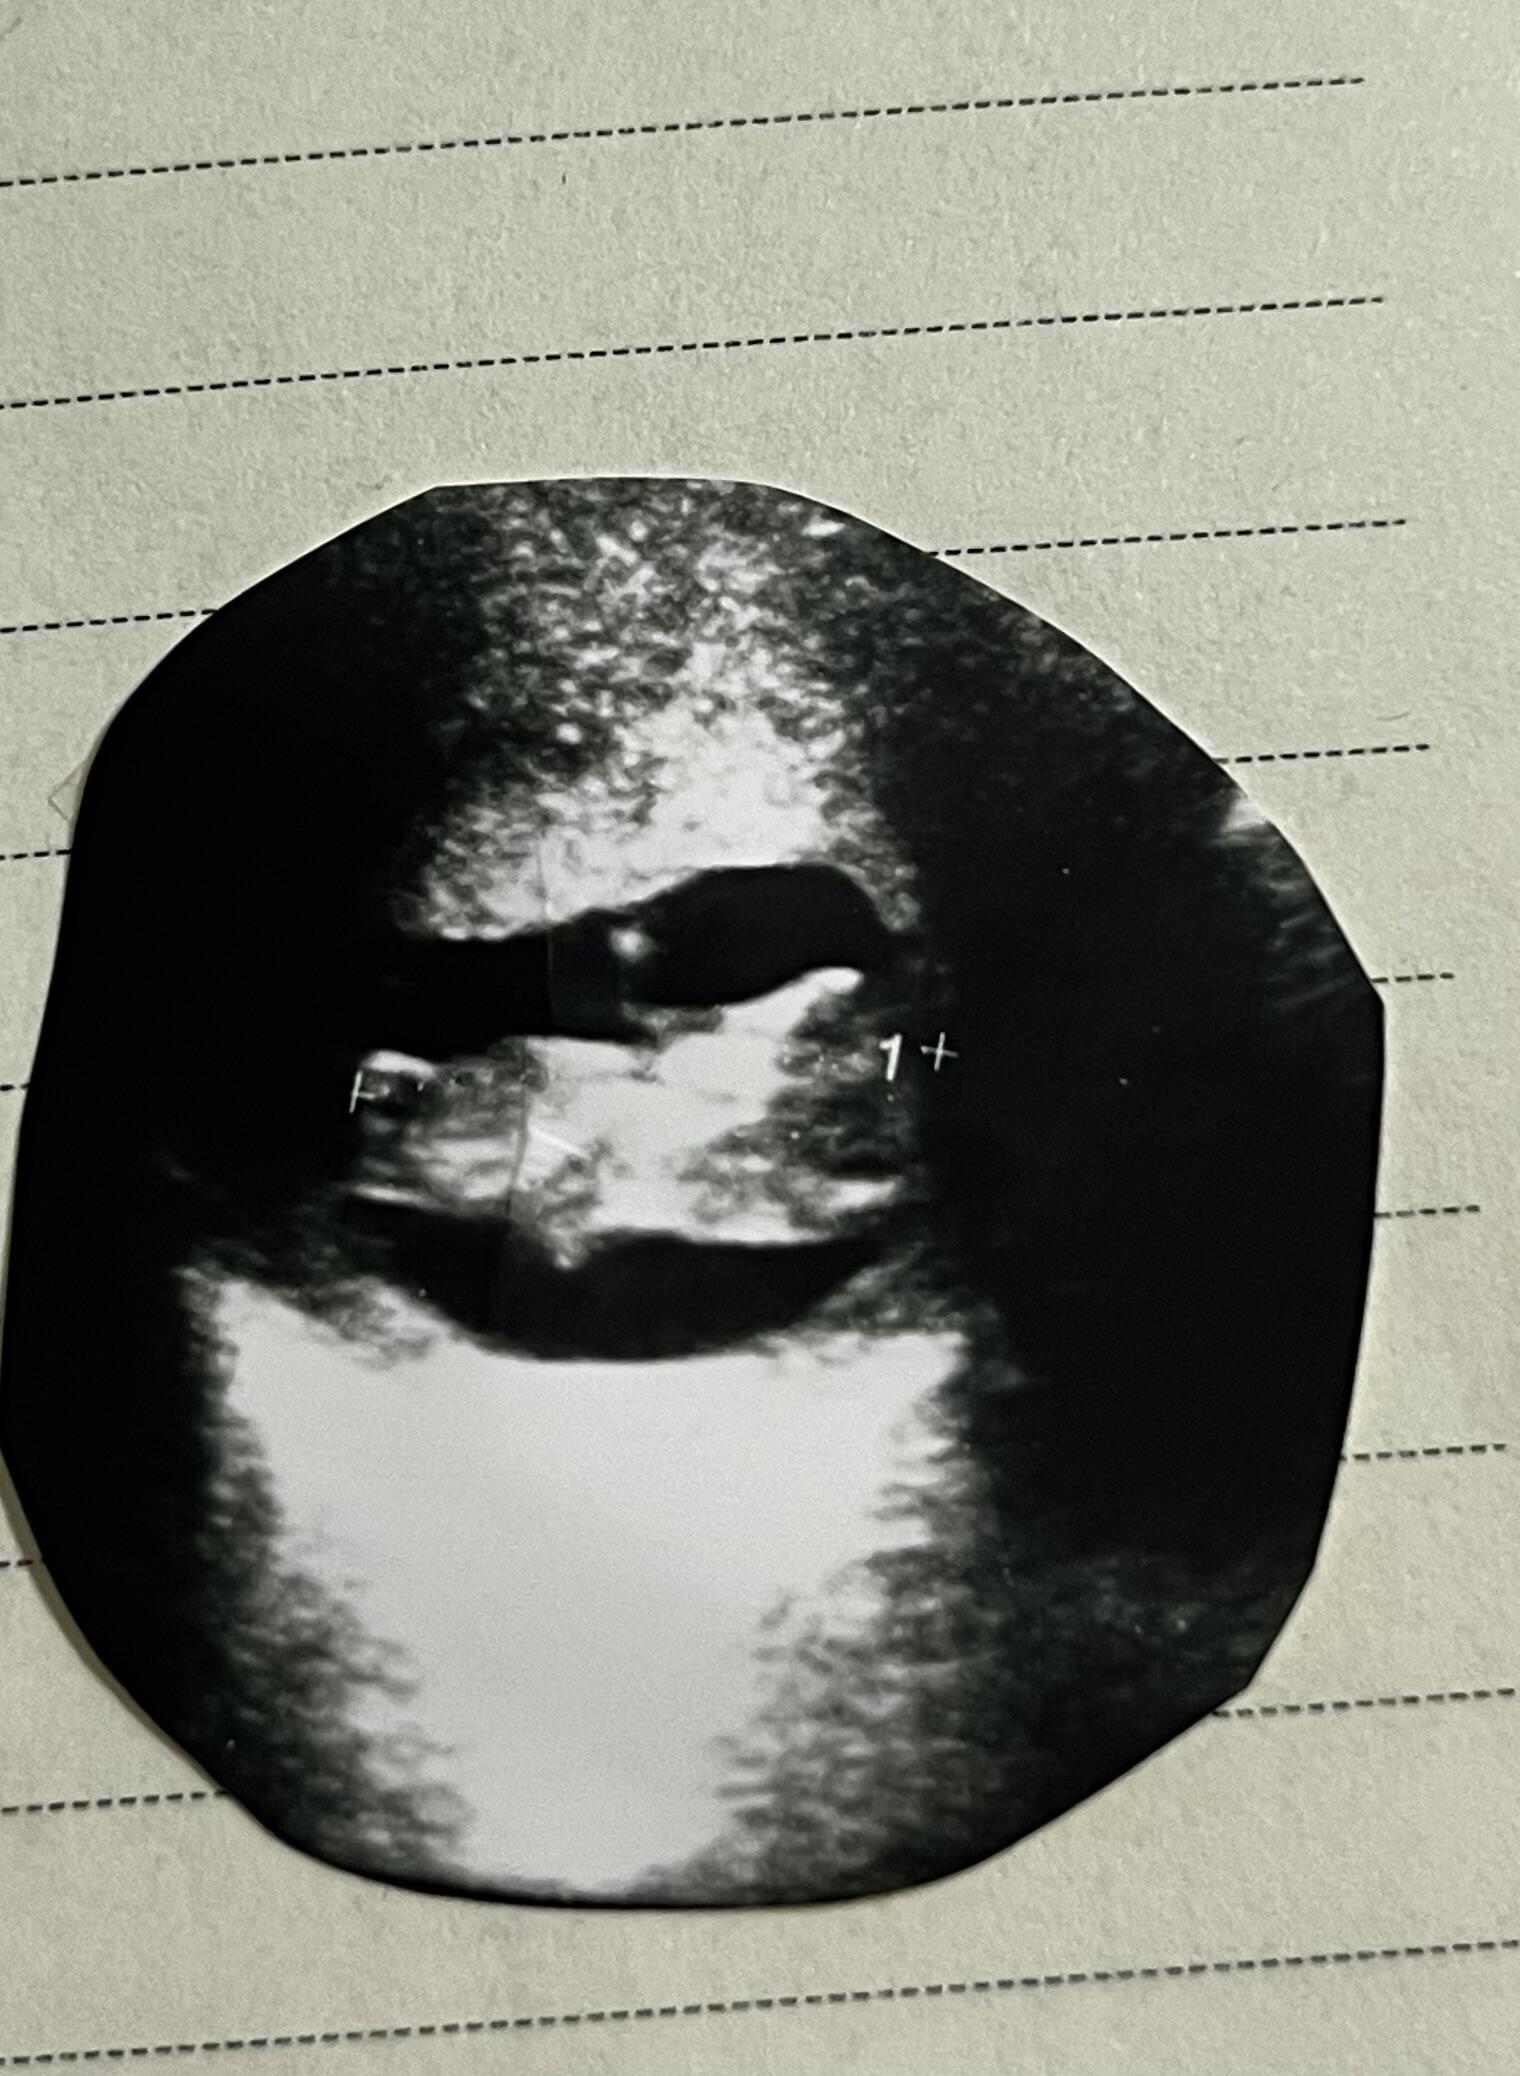

Çok minik daha ama kız gibi

Bence kiz